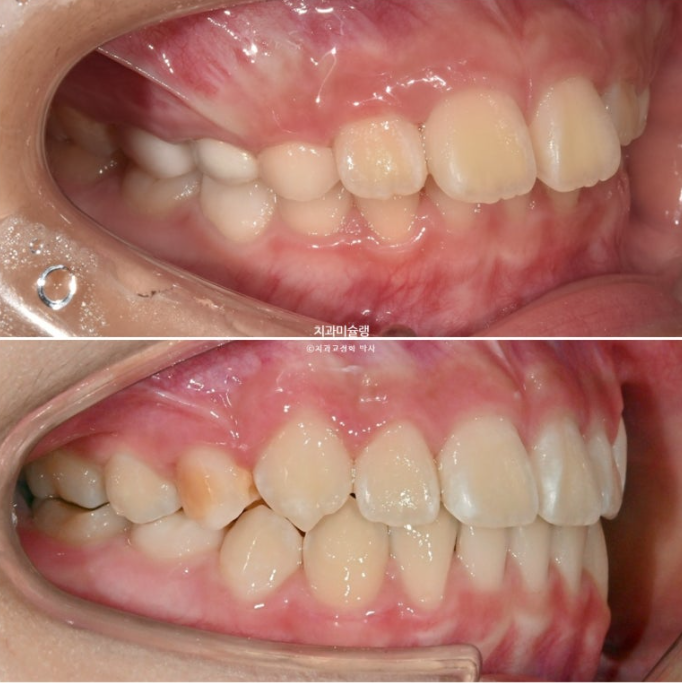

23.10~25.11

완성된 교합은 1급 교합관계를 보입니다.

나중에 성인이 되어 2차교정을 안해도 될 정도의 완성도 입니다.